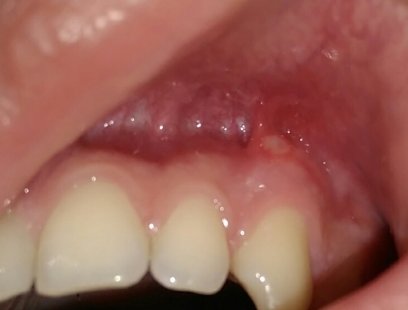

Подскажите, пожалуйста. Болела десна около недели, незначительно. Позже образовался какой-то шарик, похожий на прыщик. А после, во время еды что-то стало мешать и вот появилось непонятное новообразование из десны. На ощупь твердое, беспокоит во время приема пищи.

Подскажите, что это может быть?

Очень сложно определить, но все Ваши симптомы говорят и свищевом выходе. То есть, на верхушках зуба имеется воспалительный процесс.

Необходимо обратиться к врачу, сделать рентген-снимки и выявить точную причину.